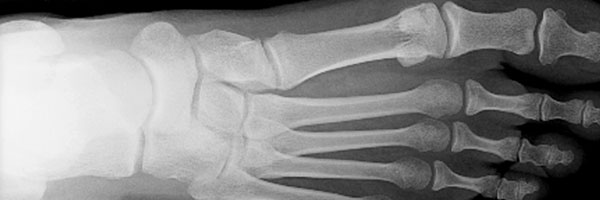

The toe bone's connected to the...

...foot bone, in case you don't remember the song.